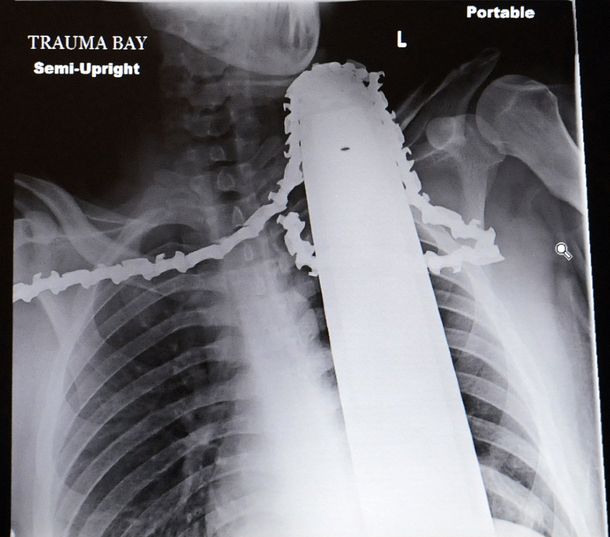

Se clavó una motosierra en el cuello y logró salvarse por muy poco.

James fue trasladado al Hospital General de Allegheny, donde fue operado con éxito y salvó su vida de milagro ya que no le tocó la arteria carótida lo que hubiera provocado su muerte de inmeditato.